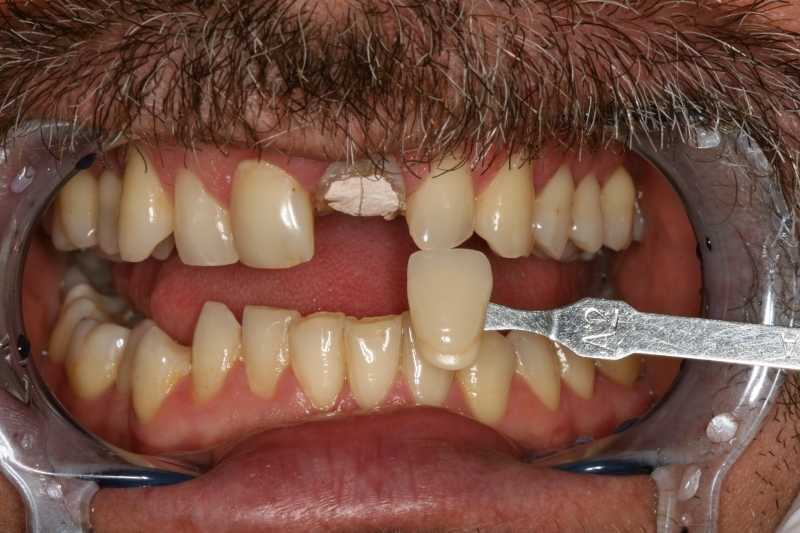

A megfelelő esztétikai végeredmény érdekében fogtechnikai laborunk nagyfelbontású fotók alapján dolgozott.

fogtechnikai laborunk nagy felbontású fotók alapján dolgozik